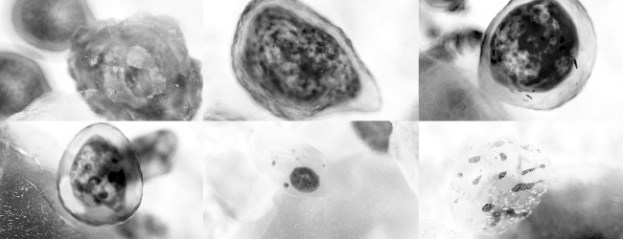

Если раскрутить кровь на высоких оборотах в центрифуге, то она разделится на отдельные фракции. ![]() Это молекулярная структура плазменного белка фибриногена, который помогает крови свертываться. Глобулины – это еще одни важные плазменные белки крови. Они образуются в печени или белых кровяных тельцах (лейкоцитах). Глобулины, как и альбумины, отвечают за транспорт различных веществ. Кроме того, они служат факторами свертывания крови (например, фибриноген), предотвращающими кровопотерю. Есть еще одна функция, которую выполняет только самый смелый тип глобулина – иммуноглобулин: он становится антителом, формирующим защитный барьер от патогенных микроорганизмов. Сыворотка Вопрос № 2: что останется, если удалить из плазмы факторы свертывания крови (например, фибриноген)? Ответ: сыворотка. Эту часть нашей крови врачи используют для определения группы крови или проверки на различные заболевания. Также плазму используют для переливания крови людям с гемофилией (их кровь не сворачивается) либо для «дозаправки» определенными иммуноглобулинами при нарушении иммунной системы. Эритроциты: трудная жизнь переносчика кислорода Эритроциты, или красные кровяные тельца, начинают свой путь в костном мозге – в промежутках губчатого вещества кости. В первые три месяца жизни эмбриона за выработку эритроцитов отвечают печень и селезенка. После необходимого внутриутробного развития и реструктуризации систем функция по образованию эритроцитов переходит к костному мозгу. Печень и селезенка остаются на скамье запасных на случай, если костный мозг перестанет справляться. ![]() Это разные стадии образования эритроцитов (эритропоэз). Когда стволовая клетка (слева вверху) готова к образованию эритроцитов, она претерпевает ряд морфологических изменений. В результате этих изменений клетка лишается ядра (справа внизу) и органелл, а также приобретает пигментный гемоглобин. После рождения все наши кости, особенно длинные, способны производить эритроциты. Этот процесс называют эритропоэзом. К двадцати годам эта способность остается лишь у избранных структур: позвоночника, грудины, черепа, тазовой кости и проксимальных концов костей конечностей. Эритропоэз Эритропоэз запускается, когда определенные клетки почек фиксируют низкий уровень кислорода в крови. Они выделяют особый гормон, или фактор роста, под названием «эритропоэтин», который стимулирует деление гемопоэтических стволовых клеток (гемоцитобластов). Эти клетки живут в костном мозге, и из них образуются все клетки крови. Далее дочерняя клетка дифференцируется в миелоидную стволовую клетку, из которой образуется ранний предшественник эритроцитов – проэритробласт. После серии изменений клетка теряет свое ядро и переносится в кровь, где становится молодым эритроцитом – ретикулоцитом. |